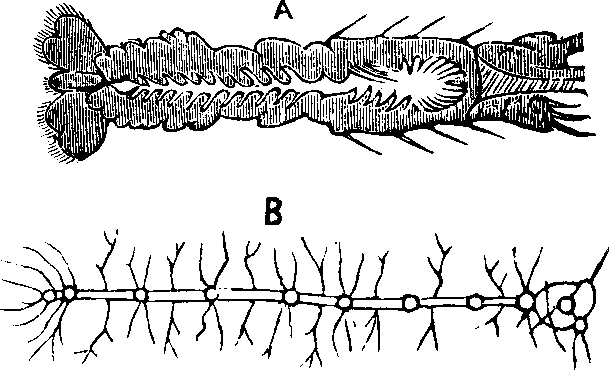

Fig. 19. Muscular fillers highly magnified.

The Muscles are those organs of the body by which motion is produced, and are commonly known as flesh. A muscle is composed of fascieuli, or bundles of fibers, parallel to one another. They are soft, varying in size, of a reddish color, and inclosed in a cellular, membranous sheath. Each fasciculus contains a number of small fibers, which, when subjected to a microscopic examination, are found to consist of fibrillæ, or little fibers; each of these fibrillæ in turn being invested with a delicate sheath. The fibers terminate in a glistening, white tendon, or hard cord, which is attached to the bone. So firmly are they united, that the bone will break before the tendon can be released. When the tendon is spread out, so as to resemble a membrane, it is called fascia. Being of various extent and thickness, it is distributed over the body, as a covering and protection for the more delicate parts, and aids also in motion, by firmly uniting the muscular fibers. The spaces between the muscles are frequently filled with fat, which gives roundness and beauty to the limbs. The muscles are of various forms; some are longitudinal, each extremity terminating in a tendon, which gives them a fusiform or spindle-shaped appearance; others are either fan-shaped, flat, or cylindrical.

Fig. 21. Striped muscular fibre

showing cleavage in opposite directions. 1. Longitudinal cleavage. 2.

Transverse cleavage. 3. Transverse section of disc. 4. Disc nearly

detached. 5. Detached disc, showing the sarcous elements. 6.

Fibrillæ. 7, 8. Separated fibrillæ highly magnified.

Every muscle has an origin and an insertion. The term origin is applied to the more fixed or central attachment of a muscle, and the term insertion to the movable point to which the force of the muscle is directed; but the origin is not absolutely fixed, except in a small number of muscles, as those of the face, which are attached at one extremity to the bone, and at the other to the movable integument, or skin. In most instances, the muscles may act from either extremity. The muscles are divided into the Voluntary, or muscles of animal life, and the Involuntary, or muscles of organic life. There are, however, some muscles which cannot properly be classified with either, termed Intermediate. The Voluntary Muscles are chiefly controlled by the will, relaxing and contracting at its pleasure, as in the motion of the eyes, mouth, and limbs. The fibers are of a dark red color, and possess great strength. These fibers are parallel, seldom interlacing, but presenting a striped or striated appearance; and a microscopic examination of them shows that even the most minute consist of parallel filaments marked by longitudinal and transverse striæ, or minute channels. The fibers are nearly the same length as the muscles to which they belong. Each muscular fiber is capable of [pg 32]contraction; it may act singly, though usually it acts in unison with others. By a close inspection, it has been found that fibers may be drawn apart longitudinally, in which case they are termed fibrillæ, or they may be separated transversely, forming a series of discs. The Sarcolemma, or investing sheath of the muscles, appears to be formed even before there are any visible traces of the muscle itself. It is a transparent and delicate membrane, but very elastic. The Involuntary Muscles are influenced by the sympathetic nervous system, and their action pertains to the nutritive functions of the body. They differ from the voluntary muscles in not being striated, having no tendons, and in the net-work arrangements of their fibers. The Intermediate Muscles are composed of striated and unstriated fibers; they are, therefore, both voluntary and involuntary in their functions. The muscles employed in respiration are of this class, for we can breathe rapidly or slowly, and, for a short time, even suspend their action; but soon, however, the organic muscles assert their instinctive control, and respiration is resumed.